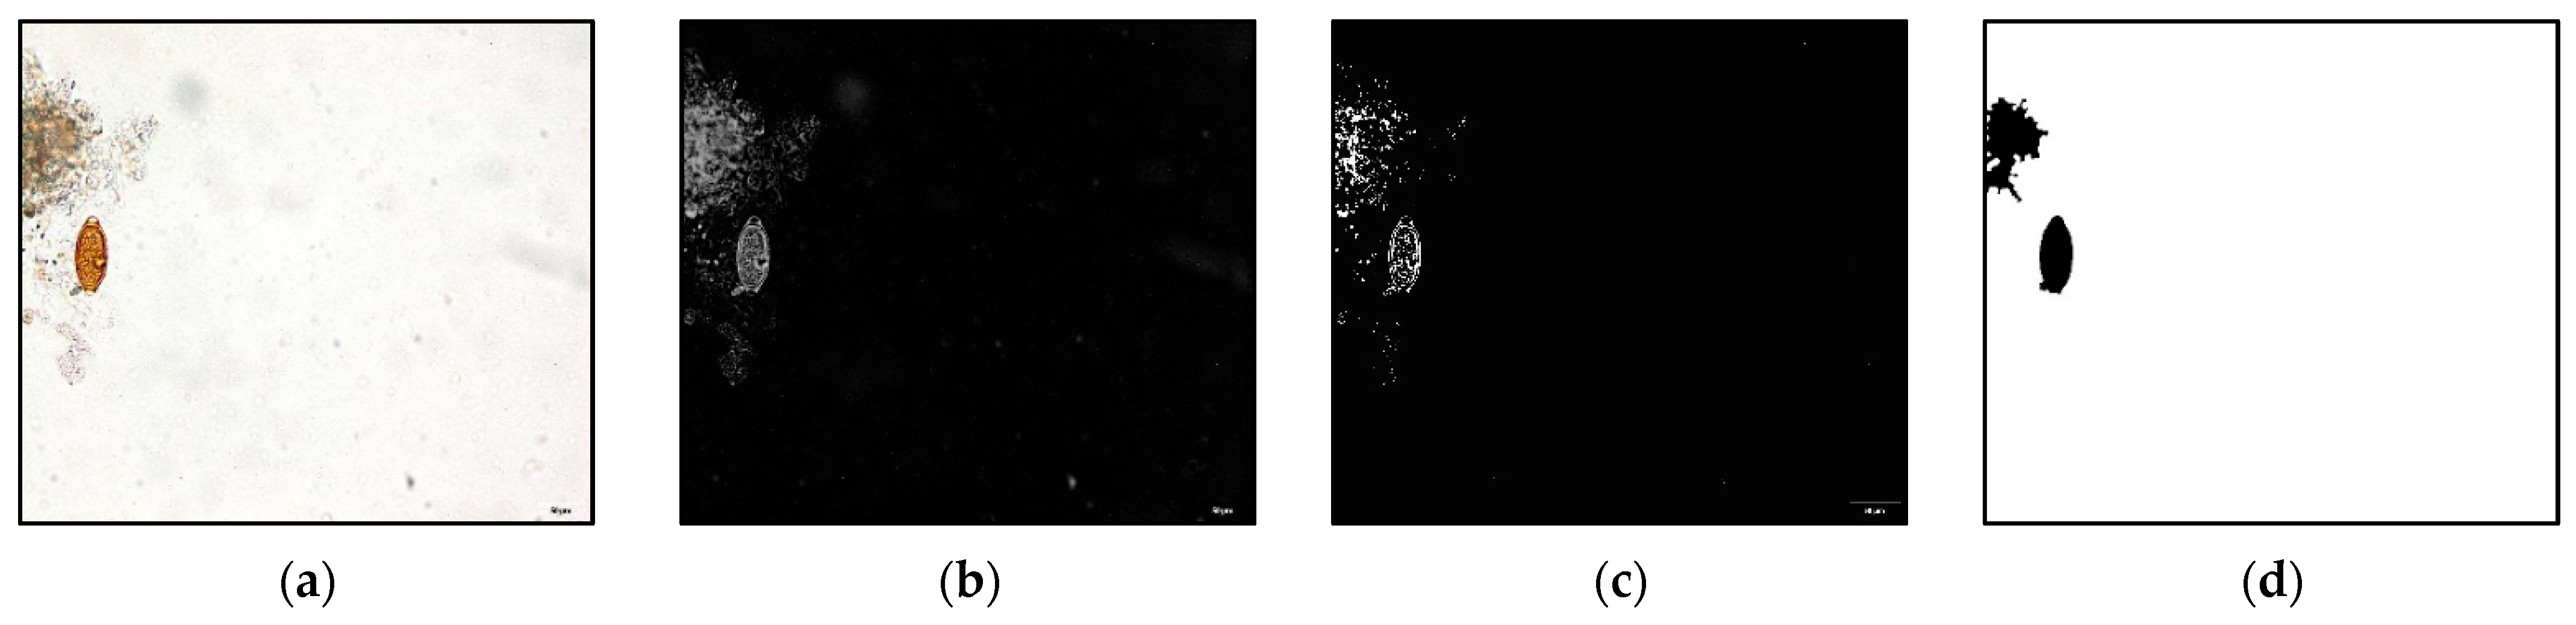

2.2. Machine Learning Segmentation Approach

2.2.1. Modified Global Contrast Stretching (MGCS)

2.2.2. Color Model

2.2.3. Fuzzy c-Mean (FCM) Segmentation

2.2.4. Post-Processing

3.1. Machine Learning Segmentation